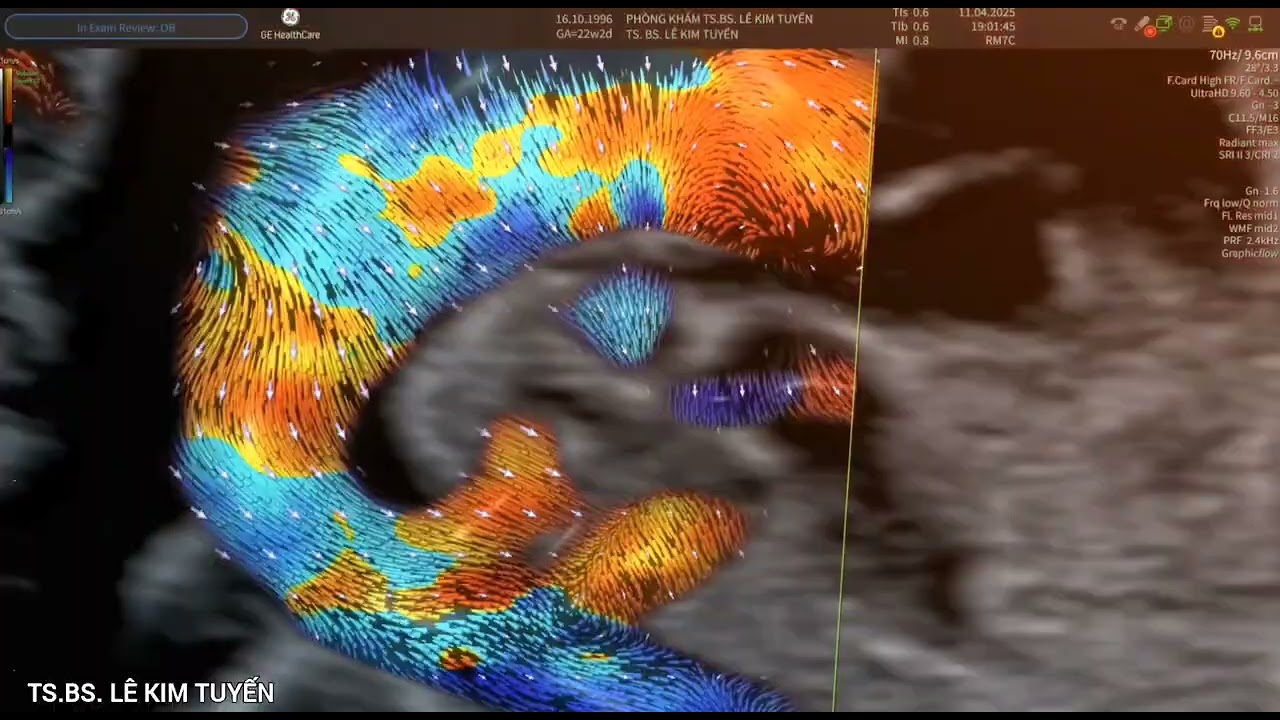

Trường hợp tim thai 22 tuần: Pulmonary Atresia with VSD (PA-VSD type IV). Được TS.BS. LÊ KIM TUYẾN thực hiện trên máy siêu âm Voluson.

Thai nhi được phát hiện không lỗ van động mạch phổi kèm thông liên thất, xếp loại PA-VSD type IV — trong đó, động mạch phổi được cấp máu chủ yếu từ tuần hoàn bàng hệ, xuất phát từ động mạch chủ hoặc các nhánh của nó (MAPCAs – major aortopulmonary collateral arteries).

🔍 Siêu âm tim thai ghi nhận:

– Không thấy dòng chảy qua van động mạch phổi

– Động mạch phổi chính nhỏ, thiểu sản hoặc không thấy rõ

– Cung động mạch chủ bên phải (right aortic arch)

→ Gợi ý nguy cơ cao bất thường vi mất đoạn 22q11 (DiGeorge syndrome)